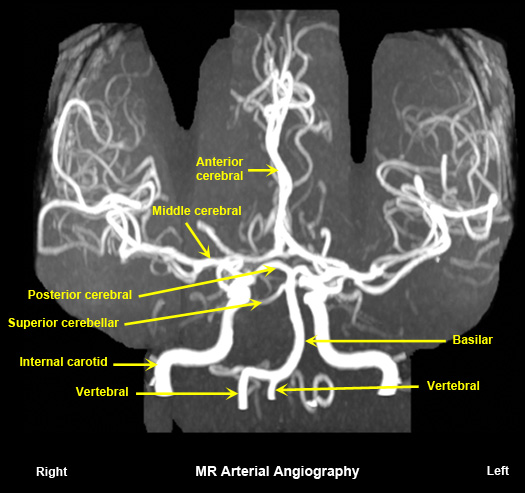

Normal MR arterial angiography

No radiation.

Contraindicated when there are metallic objects in the critical sites. |